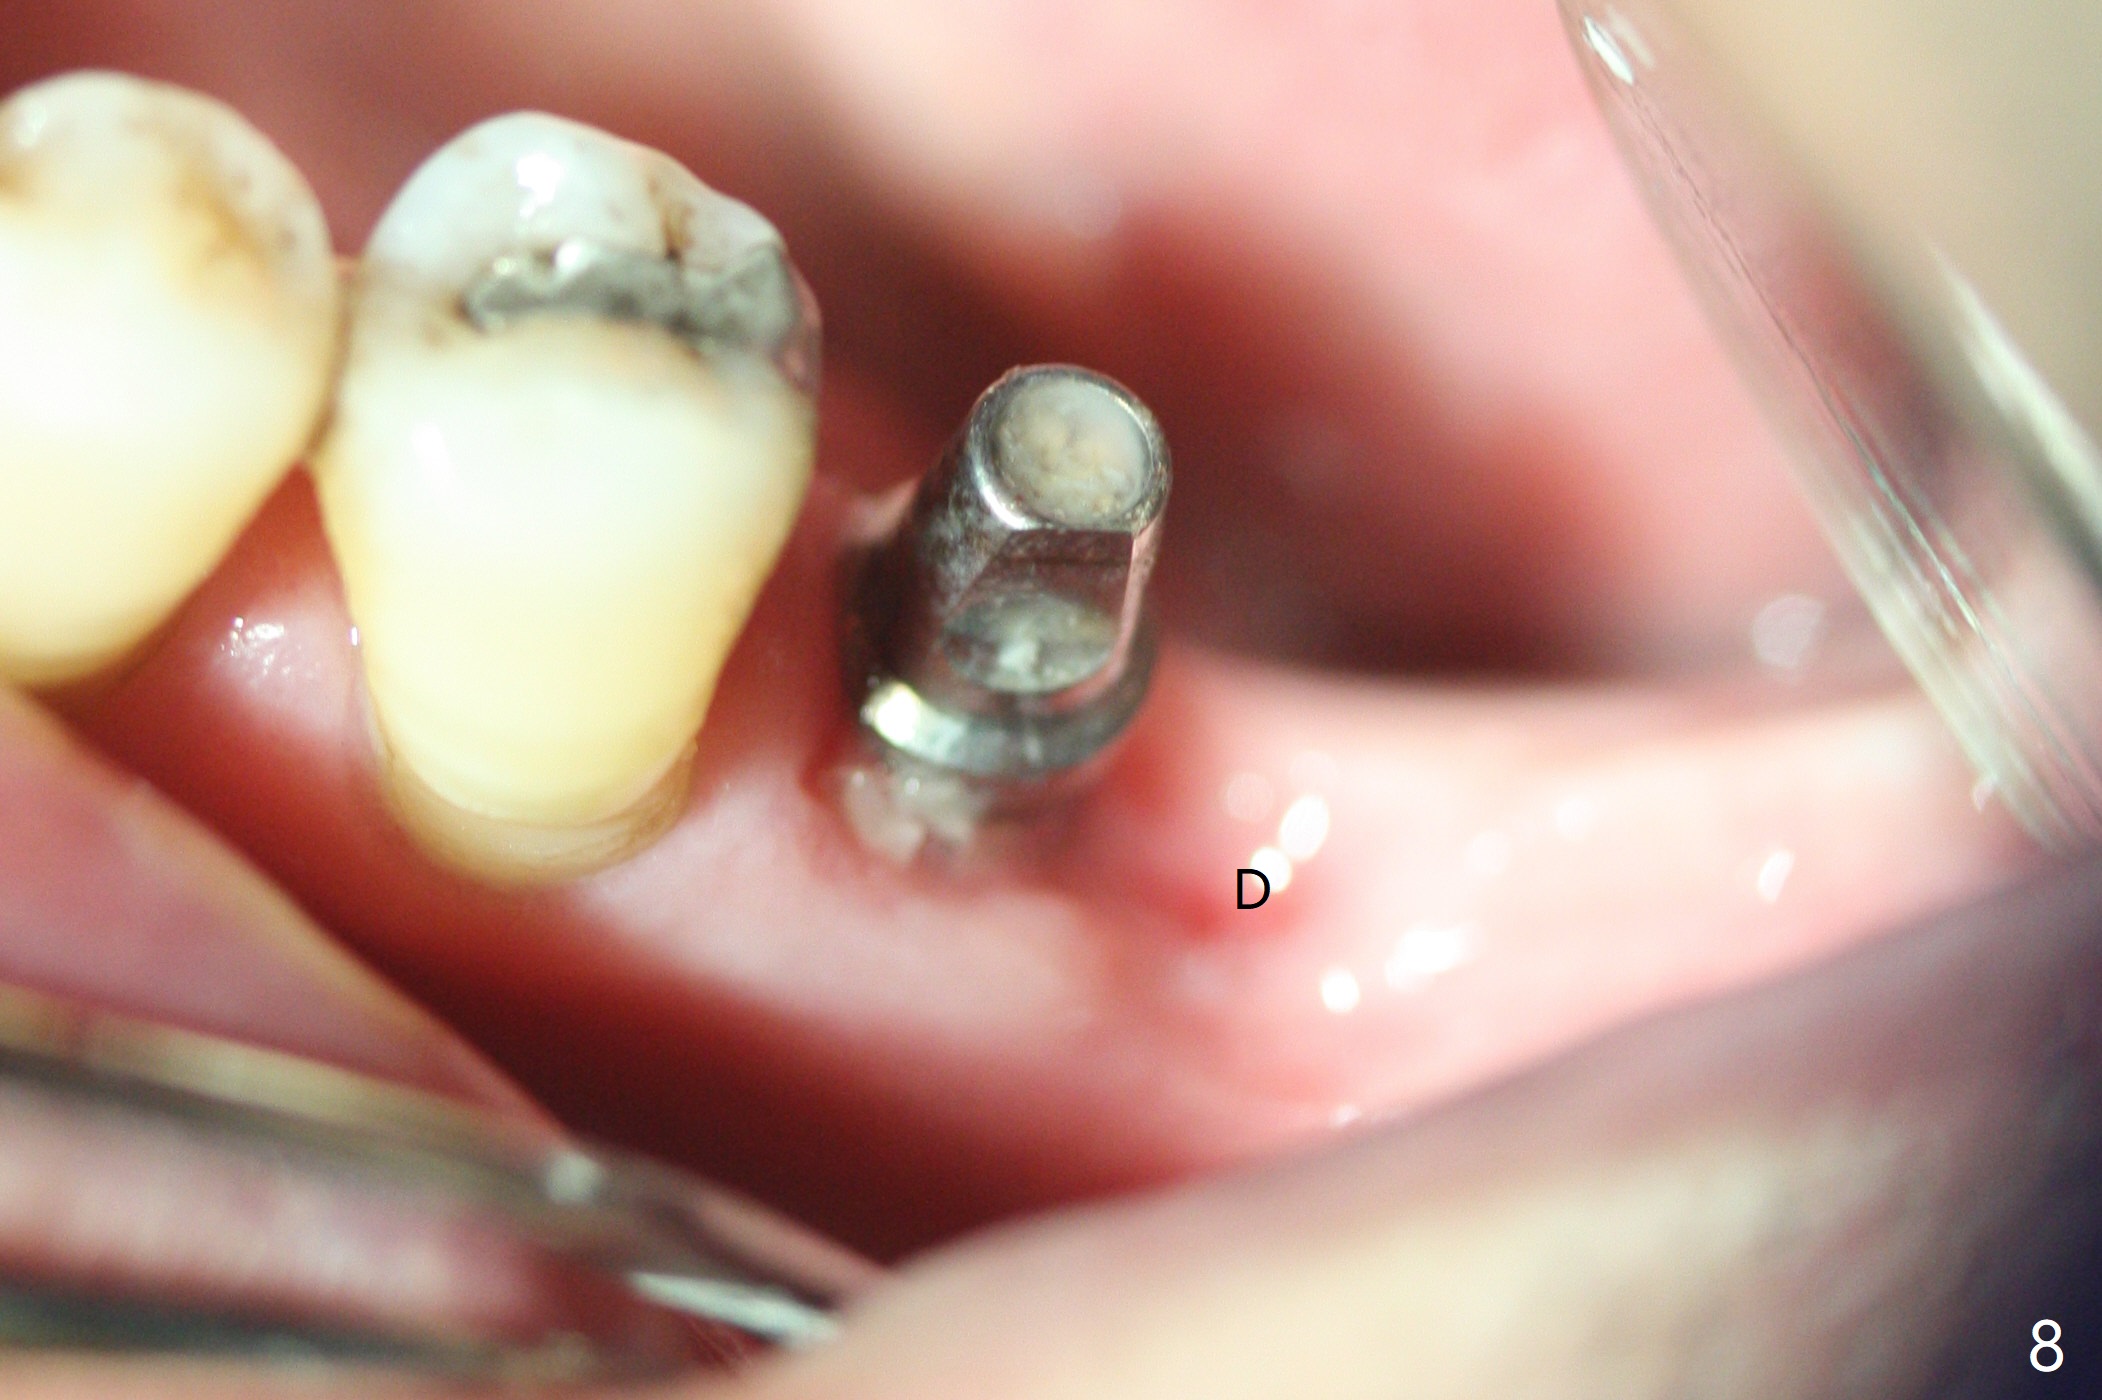

There is shrinkage in the mesial alveolus 1 month postop (Fig.6 *). When the provisional is removed 2 months postop, there is minimal amount of unincorporated bone graft (Fig.7 G) and Osteogen Plug (M, membrane). As the un-attached materials are washed up, the distal socket heals without exposure of implant threads (Fig.8 D). The bone graft settles down and remains in the distal socket 2.5 months postop (immediately pre-cementation, Fig.10 *). The bone graft appears to prevent implant threads from being exposed 2 months post cementation (Fig.11). The bone density in the distal socket increases significantly 8 months post cementation (Fig.12 *).